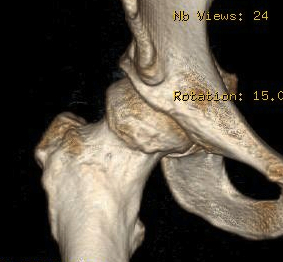

Subspine impingement

Enlarged AIIS likely from old partial avulsion

CT